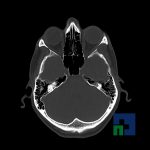

- Evaluarea cisternelor perimezencefalice

- Diagnosticul edemului cerebral, a contuziei cerebrale, a leziunilor axonale difuze edematoase/hemoragice, a dilacerării cerebrale, a hematomului intraparenchimatos posttraumatic, a hematoamelor subdurale/extradurale (acute, subacute, cronice), a hemoragiei intraventriculare, a hemoragiei subarahnoidiene

- Diagnosticul traumatismelor de bază de craniu